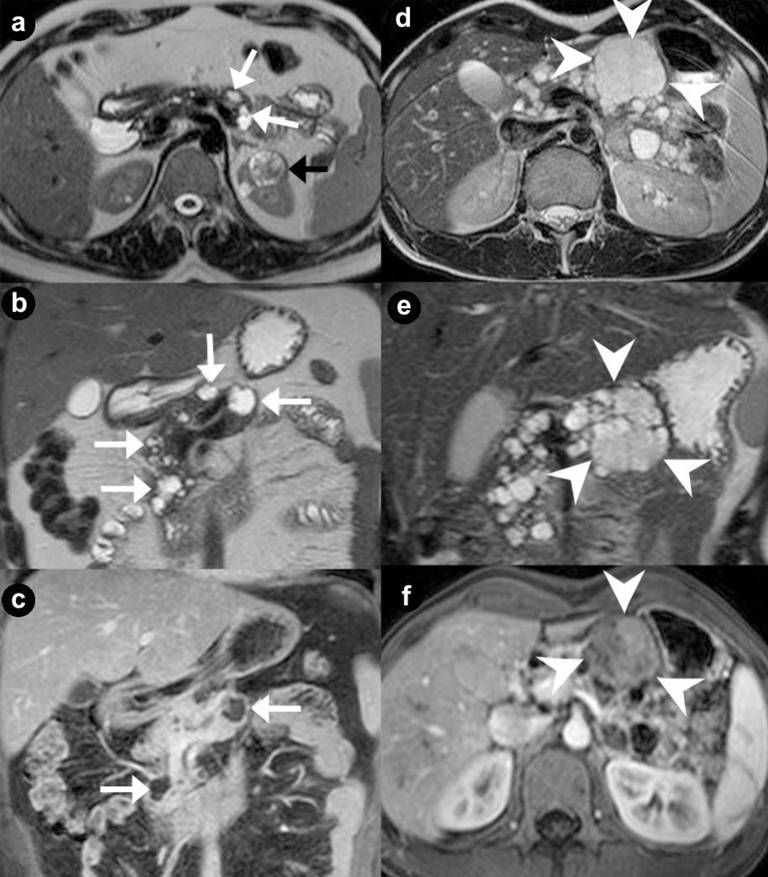

Figure 1. Pancreatic unilocular cysts (a. b. c. Case#1: 35-year-old man with VHL disease). Pancreatic microcystic serous cystadenoma (d. e. f. Case#2: 30-year-old man with VHL disease). Axial (a. d.) and coronal (b. e.) T2-weighted MR images; coronal (c.) and axial (f.) 3D volumetric gradient-echo T1-weighted fat suppressed images after intravenous contrast medium administration during arterial pancreatic phase of contrastographic dynamic study. Case#1. Multiple fluid, cystic lesions of pancreatic parenchyma with different size and site (arrows), hyperintense on T2-weighted MR images, are present (a. b. c.). Cystic lesions do not communicate with the main pancreatic duct, which appears not dilated. The cystic walls do not show enhancement after intravenous contrast medium administration (c.). In the upper pole of the left kidney (a.) a complex cystic mass (black arrow) is detected. Case#2. A lobulated fluid mass, with thin walls, hyperintense at T2-weighted images (d. e.), is present in the body of pancreatic gland (arrowheads). Inside the mass, containing multiple fluid cystic areas, multiple radially aligned thin septa are visible (spongy appearance or honeycomb pattern). The septa and the peripheral walls enhance after intravenous gadolinium administration (f.). The septa are well depicted on coronal T2-weighted MR image (e.) but the central scar is not visible. In the remaining portion of pancreatic gland multiple cystic, fluid, round lesions, with different size and site and without enhancement after intravenous contrast medium administration (f.), are present. |

Thirty-four pancreatic lesions were found in the 23 patients. In qualitative analysis, the MR imaging findings were: 6 (26.1%) unilocular fluid cystic lesions (Figure 1abc): 3 (13.0%) in pancreatic head, 3 (13.0%) in pancreatic body-tail; 11 (47.8%) serous micro- or micro/macro-cystic cystadenomas (Figures 1def, 4, and 5): 1 (4.3%) in pancreatic head, 2 (8.7%) in pancreatic body-tail (Figure 1), 8 (34.8%) diffuse (Figures 4 and 5); 8 (34.8%) neuroendocrine solid tumors: all of them non-functioning NET and hypervascular during arterial pancreatic phase of contrastographic dynamic study (Figures 2, 3, 4, and 5), 4 (17.4%) at pancreatic head (Figures 2ab; 3ace, and 4), 4 (17.4%) at pancreatic body-tail (Figures 2cd and 5); 1 (4.3%) cystic non-functioning NET, diffuse in all pancreatic gland (Figure 6); in 4 (17.4%) cases association of non-functioning NET and pancreatic cystic lesions (3 cases of association of non-functioning NET and serous cystadenoma (13.0%); 1 case of association of non-functioning NET and pancreatic simple cystic lesion (4.3%)) were present (Figures 4 and 5). Vascular invasion was not detected in any patients.

The average of maximum diameter of these cystic lesions was 44 mm (Figure 1abc).

At MR imaging [3, 9, 15, 16, 21] pancreatic cysts appear hypointense on T1-weighted images and hyperintense on T2-weighted images lesions (Figure 1ab), with no enhancement after intravenous gadolinium contrast medium administration (Figure 1c).

In microcystic serous cystadenomas, MR images [3, 15, 16, 17] show a circumscribed, encapsulated mass, with plurilobulated margins and thin walls, hyperintense on T2-weighted (Figures 1de, 4abcd, and 5abc) and hypointense on T1-weighted images, with multiple and radially aligned thin septa, hypointense at T2-weighted images. A central fibrous scar with calcification is frequently present. Peripheral wall and septa enhance after intravenous gadolinium administration (Figure 1f, 5def). The septa are well depicted on T2-weighted MR images but the central scar is not. The use of a gradient-echo pulse sequence with a long echo time may bring out the susceptibility effects from the calcified scar. So, the fluid mass results composed of a grapelike cluster or “honeycomb pattern’’ of uniformly sized cysts with a diameter of 2 cm or smaller.

In macrocystic serous cystadenoma, MR images identify a fluid lesion, unilocular or with one or rare thin septa inside lesion. The septa and thin peripheral wall of fluid lesion do not enhance after gadolinium-chelates injection during MR dynamic study (Figure 3bdf).